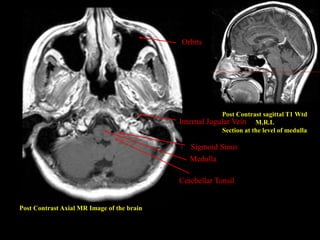

Post Contrast Axial MR Image of the brain

Post Contrast sagittal T1 Wtd

M.R.I.

Section at the level of medulla

Sigmoid Sinus

Medulla

Internal Jugular Vein

Cerebellar Tonsil

Orbits

Post Contrast AxialMR Image of the brain Post Contrast sagittal T1 Wtd M.R.I. Section at the level of medulla Sigmoid Sinus Medulla Internal Jugular Vein Cerebellar Tonsil Orbits